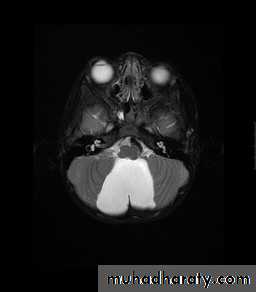

Chiari malformation:

Called also Arnold-Chiari Malformations:

Herniation of posterior fossa contents (e.g. cerebellar tonsils) through the foramen magnum.

Normally up to 5mm of tonsillar descent through the foramen magnum.

Chiari I: >5 mm of tonsillar descent.

Chiari II: descent of the tonsils and cerebellar vermis.

Chiari malformation Type I

Developmental Abnormalities of the Nervous System